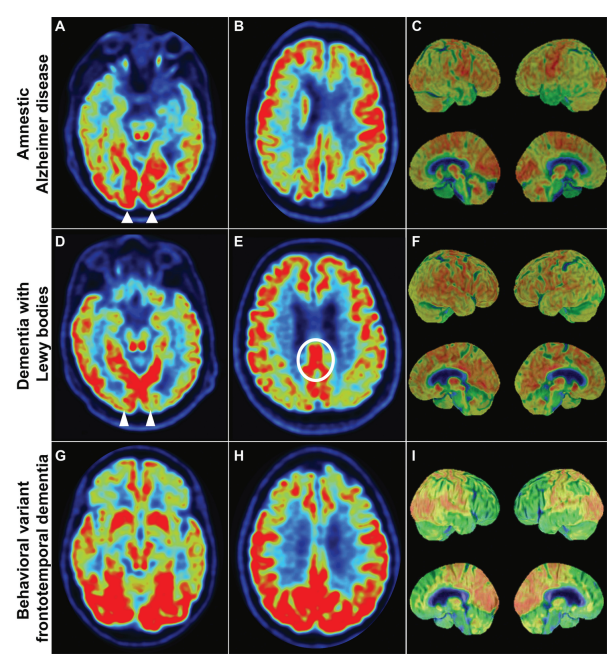

Qual doença eh qual no PET?

A

Numere cada uma das variantes de acordo com PET